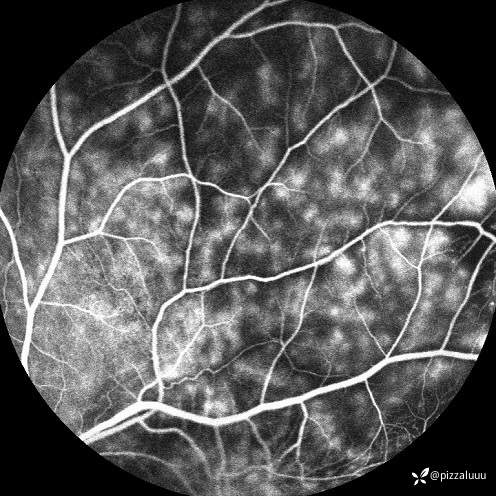

今天补充了FFA、AF和眼底照相。很典型的coats,后极部视网膜可见块状不规则而隆起的黄色渗出。AF可见病灶处低自发荧光。FFA所见:视网膜毛细血管扩张迂曲及异常血管形态,以小动脉明显,管壁呈囊样扩张,有梭形、串珠样动脉瘤。大片无灌注区。异常血管早期渗漏明显,形成强荧光斑,晚期荧光融合。由于大片黄白色渗出位于外丛状层,对视网膜血管荧光影响不大。可看到脉络膜背景荧光遮蔽。